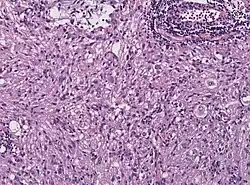

Histologisch ist dieser Tumor durch die außergewöhnliche Pleomorphie, d. h. eine Vielgestaltigkeit der glialen Tumorzellen charakterisiert. Mitosefiguren kommen vor, Nekrosen werden jedoch (im Gegensatz zum Glioblastom) gewöhnlich nicht beobachtet. Die Tumorzellen können Lipideinlagerungen enthalten (xanthomatöse Umwandlung) und sind von Retikulinfasern umgeben. Die immunhistochemische Färbung für GFAP belegt den glialen Charakter des Tumors.[6] Obwohl aufgrund des charakteristischen histologischen Bildes die diagnostische Abgrenzung gegenüber anderen Hirntumoren gewöhnlich keine Schwierigkeiten bereitet, kann die ausgeprägte Pleomorphie des Tumors insbesondere in der intraoperativen Schnellschnittuntersuchung zur Fehldiagnose eines Glioblastoms verleiten.